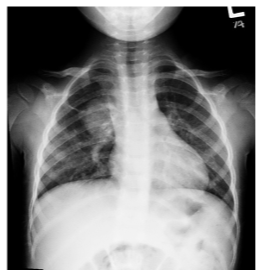

Paciente de sete anos, do sexo masculino, apresenta tosse e febre há cinco dias. Ao exame físico, observa-se prostração e frequência respiratória de 48 IRPM. À ausculta, nota-se presença de estertores finos (crepitantes) em campo médio direito. A radiografia de tórax em PA é evidenciada a seguir.

Enunciado 3935120-1

Nesse caso, a etiologia é: